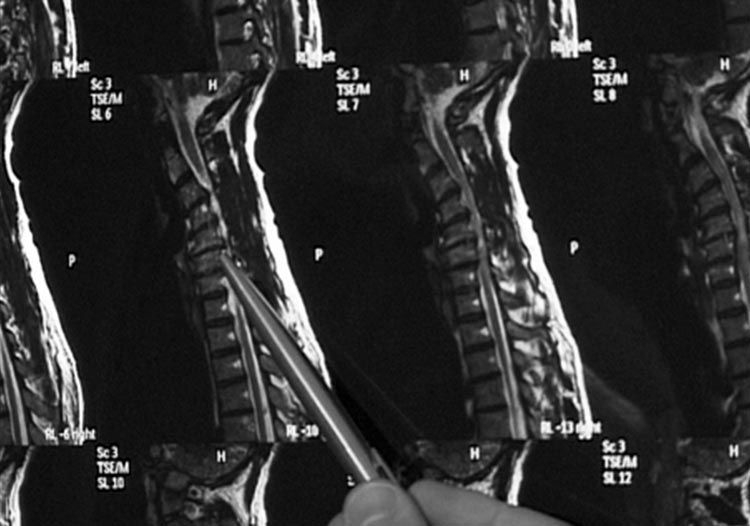

Die Twin Tagesklinik für Wirbelsäulen und Neurochirurgie unter der Leitung von Dr. Al Nahlaoui ist Ihr kompetenter Partner zur Erhaltung der Beweglichkeit sowie Befreiung von Rücken- und Nervenschmerzen.

Moderne Diagnostik und Beratung sowie konservative und operative Behandlung gehören zum umfangreichen Leistungsangebot der Praxis. - www.nahlaoui.de